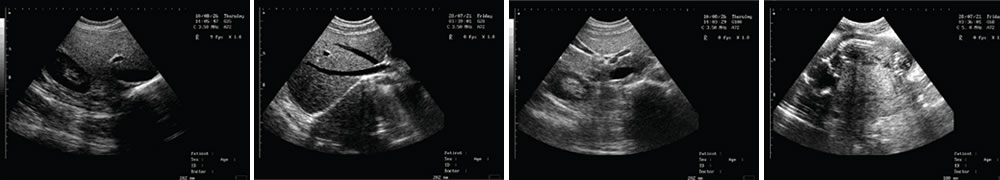

LED高清晰顯示器 一流的數(shù)字成像技術(shù)

V-218全數(shù)字筆記本式動物超聲診斷儀(動物版)一流的數(shù)字成像技術(shù),圖像更清晰